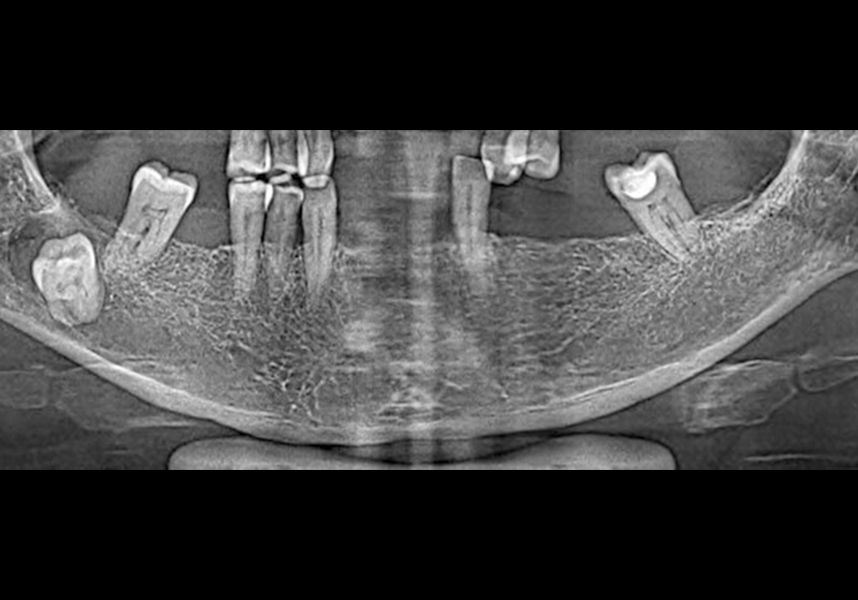

Patient aged 58 years, non-smoker, with allergy to Enantyum and effervescent medicines being the only aspects of interest in her medical history, consulted the clinic to replace her lower removable prosthesis she used due to various absent teeth in the anterior sector, third and fourth quadrants, with a fixed restoration.

In the initial intraoral examination we observed an alveolar ridge that was optimum at coronal level, but with presence of significant bone concavity in the apical at anteroinferior level.